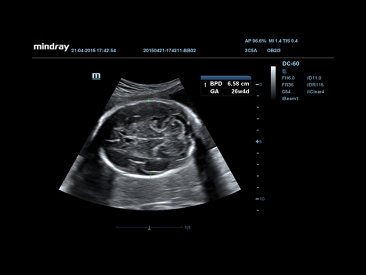

Smart OB?

Auto measurement of fetal parameters: trace and calculate the BPD, OFD, HC, AC and FL on a single click.